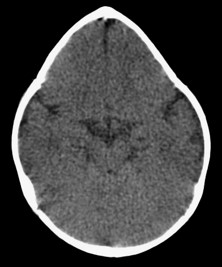

Mas doutor, quando é preciso de tomografia do crânio? Quase nunca, é solicitado quando existe alguma dúvida e mais ainda nas craniossinostoses sindrômicas.

> Escafocefalia, é a sinostoses mais comum, vista mais no sexo masculino,o que acontece é o fechamento da sutura sagital levando o crânio ao formato de barco. A cirurgia é indicada de preferencia antes do sexto mês de vida, mas se a criança tiver mais idade, não impede de ser operado.

> Trigonocefalia, é o fechamento precoce da sutura metópica, o formato do crânio é em forma de pera o qual realiza compressão do lobo frontal que pode levar aumento da pressão intracraniana em até 20% dos casos. Crianças com mais de 5 anos que não foram operados, tem literatura que fala em dificuldade do aprendizado.

> Plagiocefalia, é o fechamento precoce da sutura coronal unilateral (plagiocefalia anterior) ou da sutura lambdoide (plagiocefalia posterior), afeta mais o sexo feminino e o lado direito é mais afetado. A criança tem um rostro em “arlequim” já que uma das órbitas esta retraída para cima e para tras.